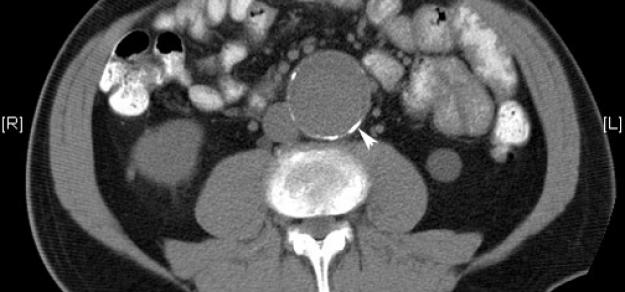

Prescripción de metformina y aneurisma aórtico

03 abril 2019

Heart, 1 de abril de 2019 la prescripción de metformina podría limitar la expansión de la AAA entre los pacientes con esta enfermedad, y podría estar involucrada con una menor incidencia de aneurisma aórtico y eventos de aneurisma aórtico